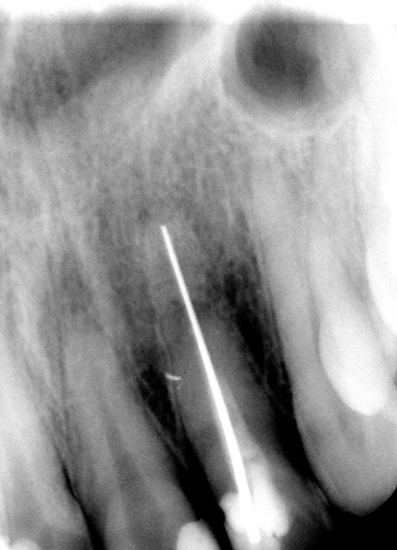

А что это у меня в канале находится?

это зуб передний у меня очень потемнел

Елена, здравствуйте.Этот зуб, наверное, уже давно лечили,т.к. это старая методика постановка серебряного штифта в канал зуба.Что можно сделать...К сожалению, полностью извлечь его не получится,т.к. резать в тонком канале в слепую-опасно. Можно продырявить корень и тогда зуб нужно будет удалять.Есть два варианта- попробовать внутриканальное отбеливание, которое заметно осветлит коронку зуба. Но дать гарантию, что это точно поможет- сложно,т.к. не понятно, как отреагирует штифт на такое вмешательство.Можно попробовать, а если не получится- просто выпилить часть штифта, поставить вкладку и коронку.

Больше похоже на проекцию гайморовой пазухи.Винир нельзя. Ненадежная конструкция в Вашем случае.

А расскажите пожалуйста уж очень интересно,а зачем раньше серебряный штифт в канал вставляли?Кстати,некоторые врачи пытались разпломбировать канал,но ничего у них нет выходило!! Кто-то из врачей мне сказал,что его цементом залили,поэтому и не разпломбировывается.А там оказывается иголка какая-то!!